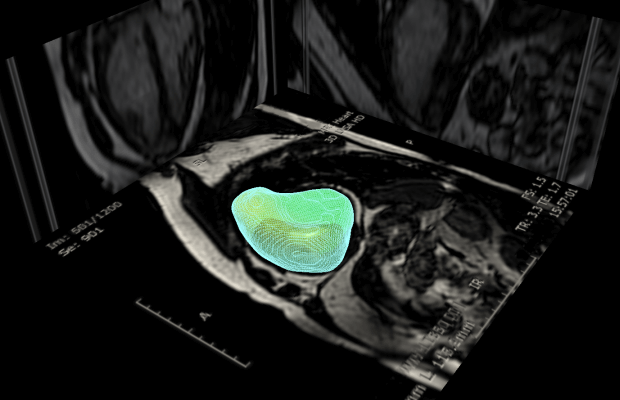

The computer program, called 4Dsurvival, takes each patient’s scan and tracks the motion of the heart at hundreds of points every second. From these 3D pictures of the moving heart the machine learns to predict the risk of dying from heart failure.

So far, the team at Imperial College London and the Medical Research Council have used the technology to predict the prognosis for 302 people with a heart condition called pulmonary hypertension (PH) a rare but serious condition, which damages the arteries in the lungs, and can be fatal.